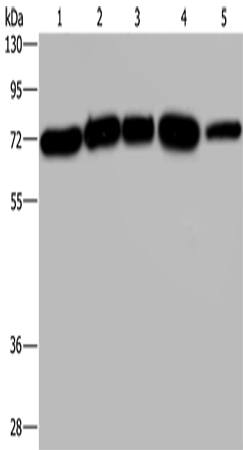

分类: 科研抗体货号: P07767别名: ACATE2; CGI-16; MTACT48; MT-ACT48应用: WB反应种属: Human, Mouse